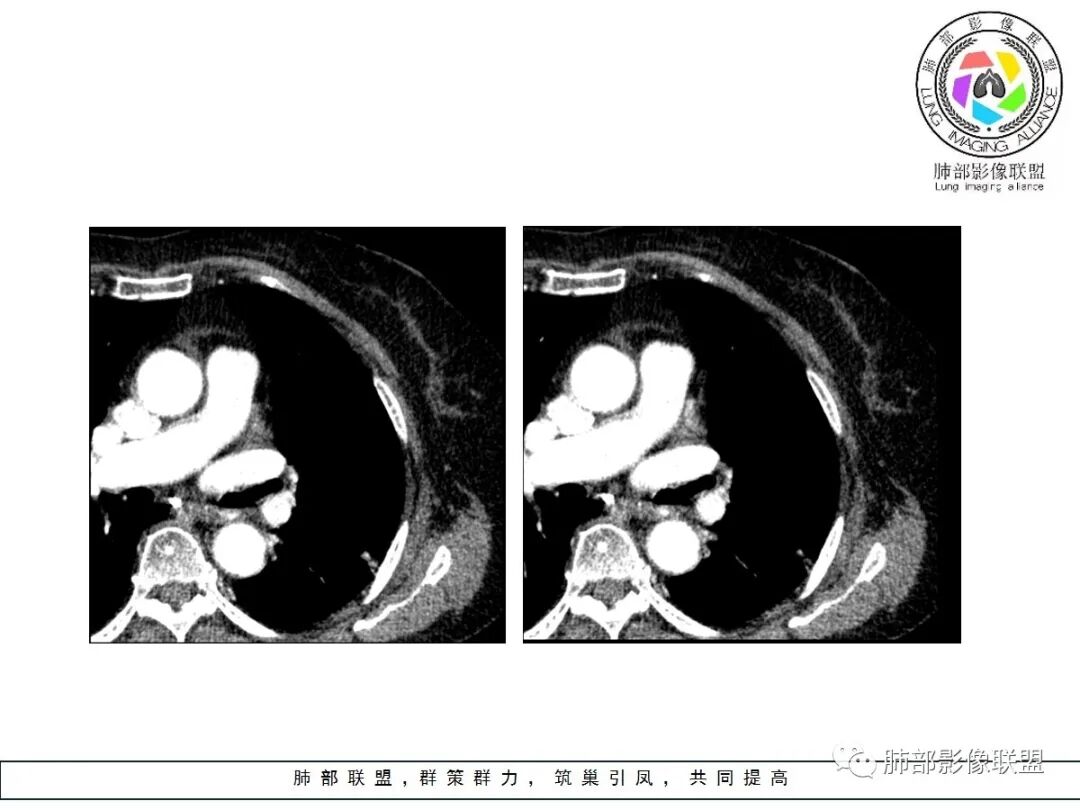

这条血管让我不踏实,像脐凹征吗?

其他的都是炎性特点,恶性待排吧

就是这个脐凹征有恶性的特点,所以恶性肯定不能排除

一、本例恶性征象较有特征的是脐凹征。

1.脐凹征:分叶状结节局部凹陷的部位受到血管阻力而形成,表现为血管进入分叶之间,脐凹相对比较对称光滑,近肺门侧多见,与血管走行方向一致。

2.95%见于恶性肿瘤,5%为炎性病变。